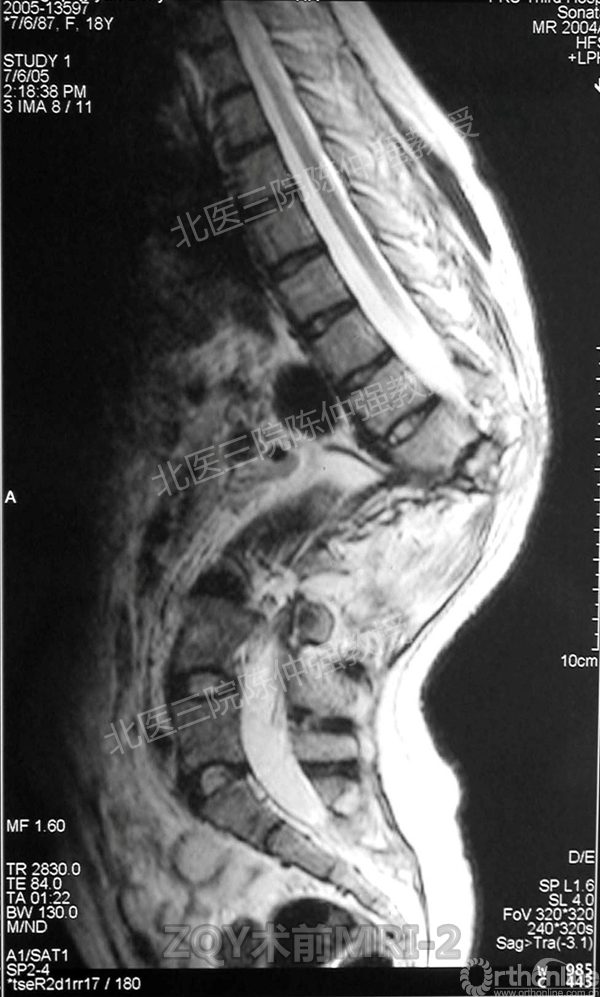

2005年,陈仲强教授在AOSpine年会上分享了一例胸腰椎陈旧结核性侧后凸畸形病例。资料如下:

ZQY术前

患者女性17岁,胸腰椎陈旧结核性侧后凸畸形,局部呈“麻花状”扭转,无神经功能受损表现。2005年,陈仲强教授带领团队实施后路+侧前方联合入路脊柱节段切除、双轴旋转矫形术。术后患者外观显著改善,神经功能正常。术后随访证实患者截骨矫形节段骨性融合良好,矫形效果持续良好。